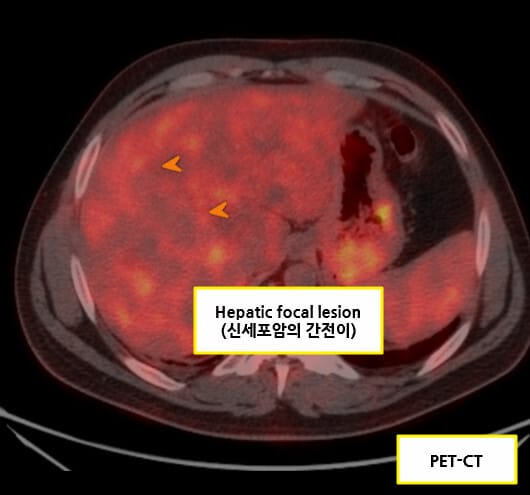

| ✅ 폐 또는 뼈 전이 |

| 흉부 CT에서 다발성 폐 결절, 골스캔에서 골 전이 소견이 있을 수 있습니다. |

Renal cell carcinoma 병기

신세포암(Renal cell carcinoma, RCC)의 병기는 종양의 크기와 신장을 넘는 침범 정도, 림프절 전이 여부, 원격 전이 여부에 따라 TNM Staging 체계로 분류합니다. 병기는 예후 예측과 치료 결정에 매우 중요합니다.

| Stage IV (T4 또는 M1) |

| 종양이 인접 장기(부신, 대장 등)를 침범하거나, 원격 전이(폐, 뼈, 간 등)가 있는 경우. |

Stage IV

T4 또는 M1: 종양이 주변 장기 침범 또는 원격 전이가 있는 경우